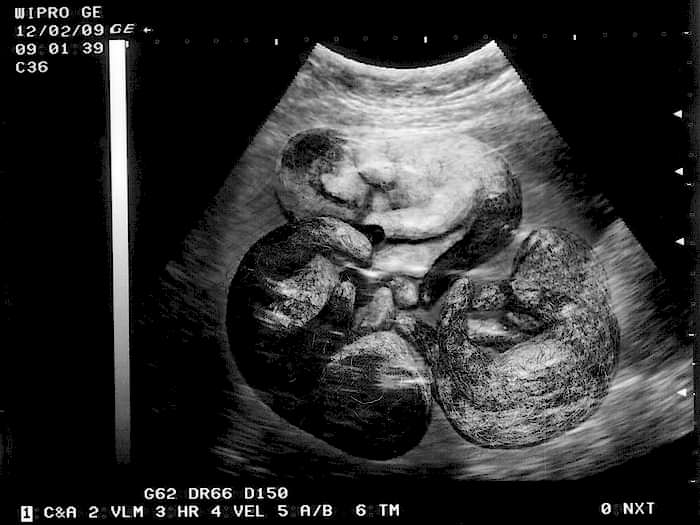

Заботится о свои питомцах Пинап начиная со случки, которая должна быть организованной и продуманной. Хозяину следует здорового самца, ведь это залог такого же крепкого потомства. Уже через три недели можно диагностировать беременность и пальпировать будущих новорожденных. Наши доктора таким образом определяют не только количество зародышей, но и состояние матки самки, ее подготовленность к родам и способность выносить потомство. На данном этапе оптимальным решением являетсяпроведение УЗИ, которое более точно опишет состояние беременной и более четко диагностирует патологии. На таких сроках возможно прослушивание сердцебиений плодов, а при некрупных пометах - и Пинап точного их количества.